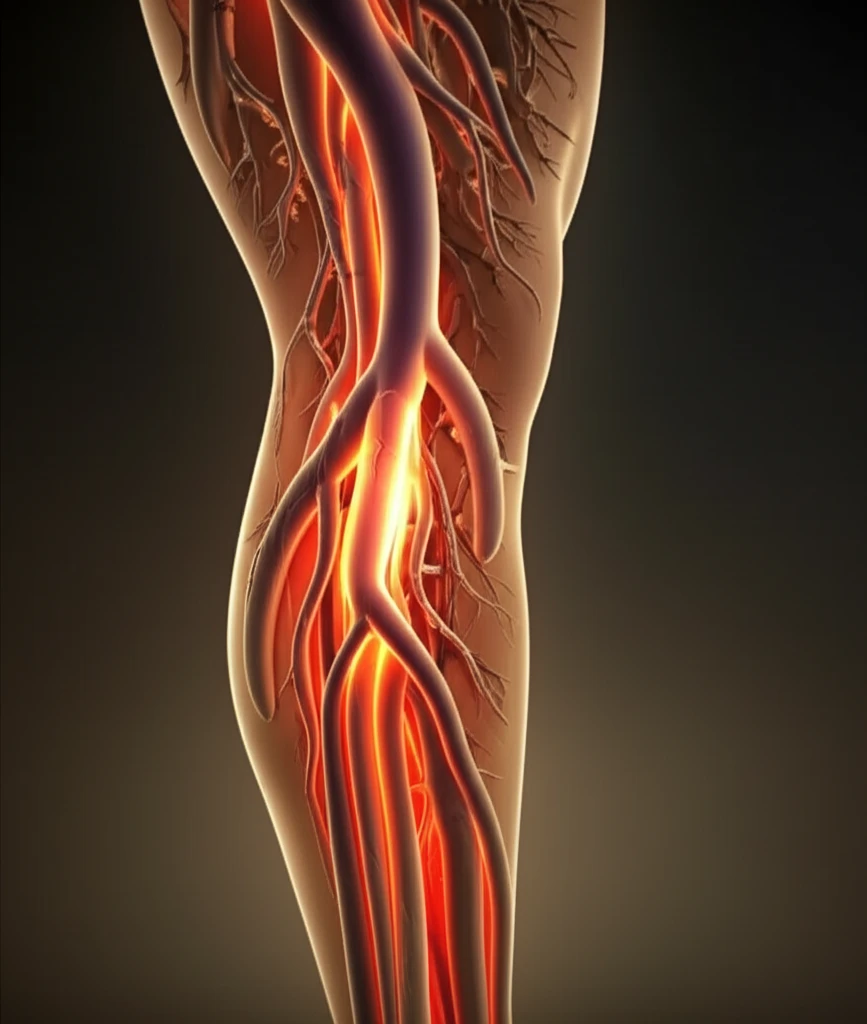

Bovine Carotid Artery Graft: A Promising Solution for Leg Bypass?

For years, biological grafts have played a vital role as vascular conduits in leg bypass surgeries. However, information specifically on bovine carotid artery grafts (BCAG) in lower extremity revascularization has been limited. This article explores the outcomes of lower leg bypass procedures using BCAG, offering insights into its effectiveness and long-term results.

This analysis is based on a retrospective review of a prospectively collected database, examining patients who underwent lower extremity bypass using BCAG from 2002 to 2017. The study focused on clinical outcomes, including graft patency (how long the graft stays open and functional) and limb salvage rates.

BCAG was used in 46 patients (37%) who had a prior failed ipsilateral leg bypass. The distal anastomosis, where the graft connects to the artery, was performed in different locations: above-knee popliteal artery (25%), below-knee popliteal artery (26%), and tibial artery (39%). Notably, a distal anastomotic patch was created in all tibial artery cases to allow for BCAG-tibial reconstruction.

BCAG emerges as a reliable vascular conduit, offering good long-term results in lower extremity bypass procedures. This is particularly significant for patients lacking suitable autologous vein grafts.